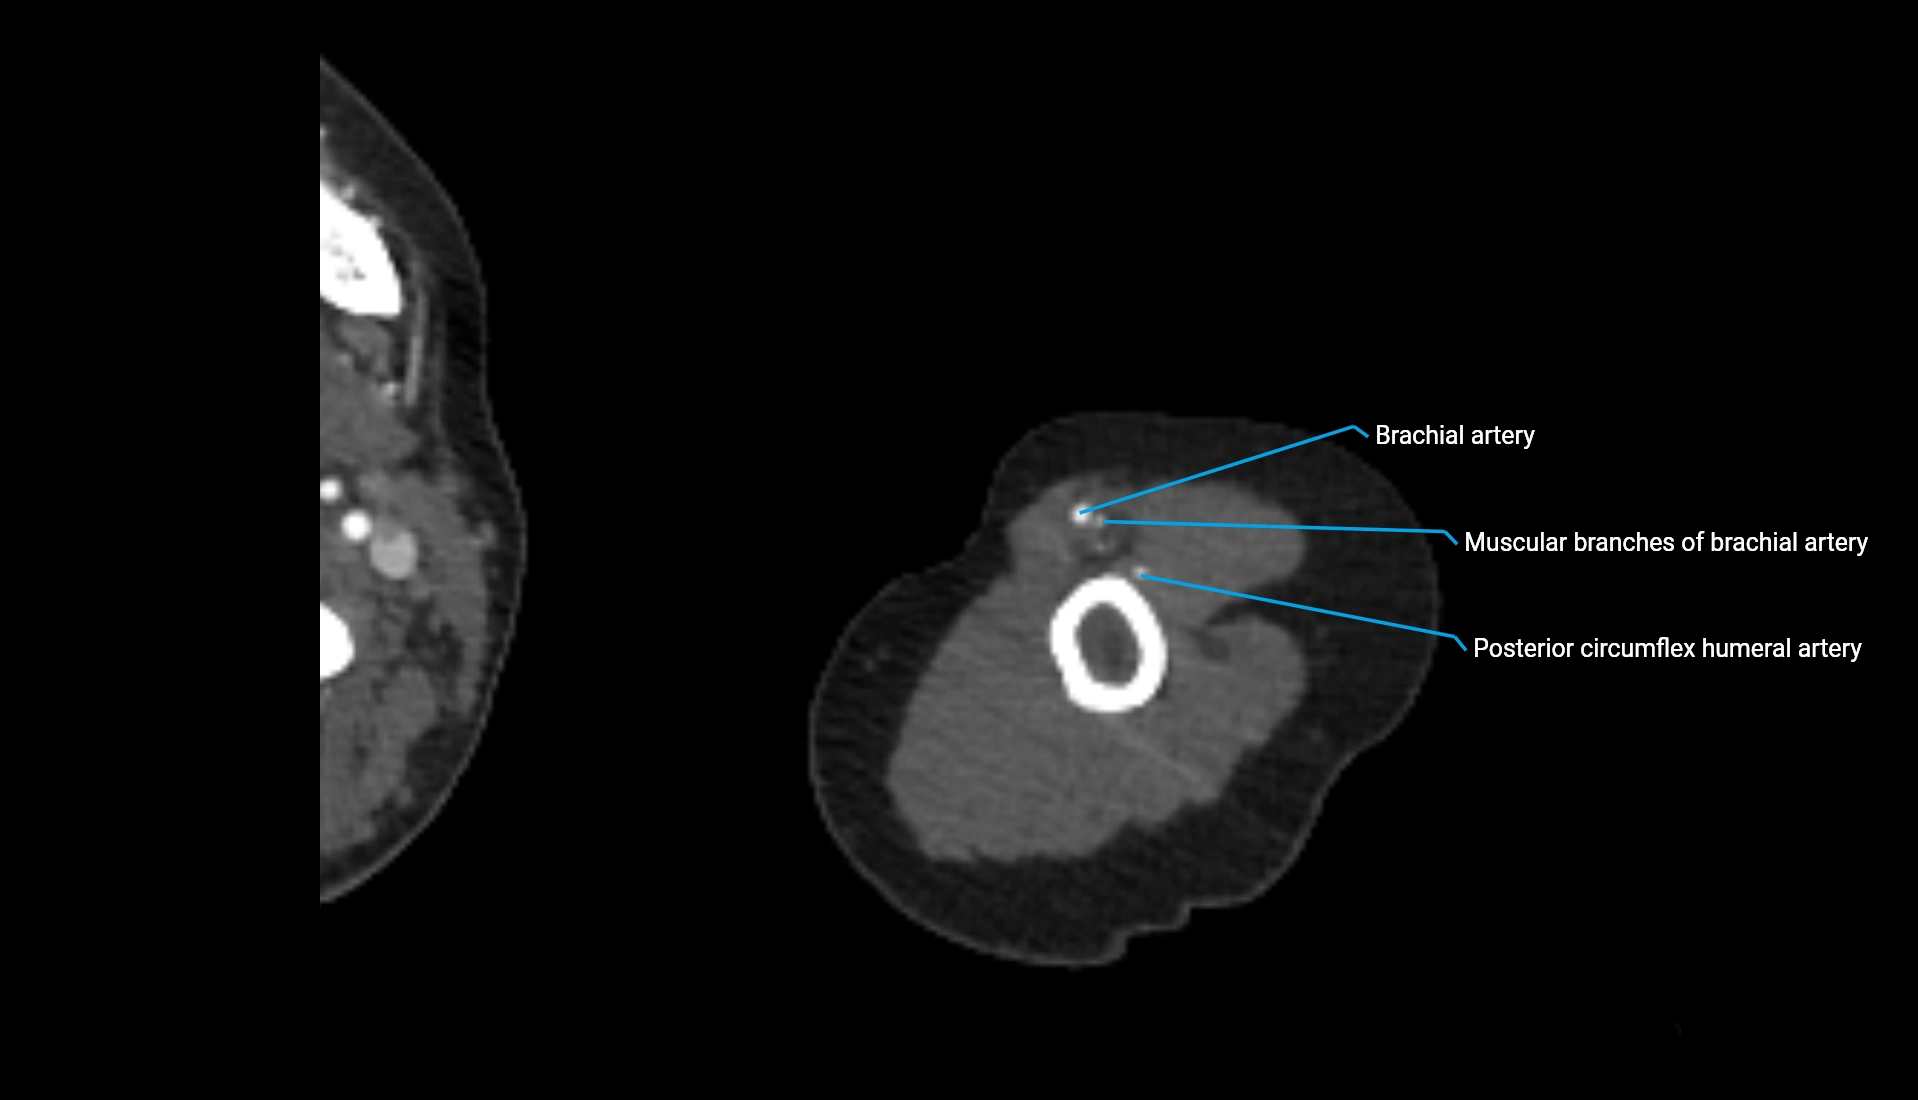

CT Appearance

Non-Contrast CT:

• Cortex: High-density, sharply defined

• Subchondral bone: Dense cancellous matrix

• Articular surface: Smooth concave contour articulating with the capitellum

• Excellent for evaluating bone integrity, alignment, and subtle fractures